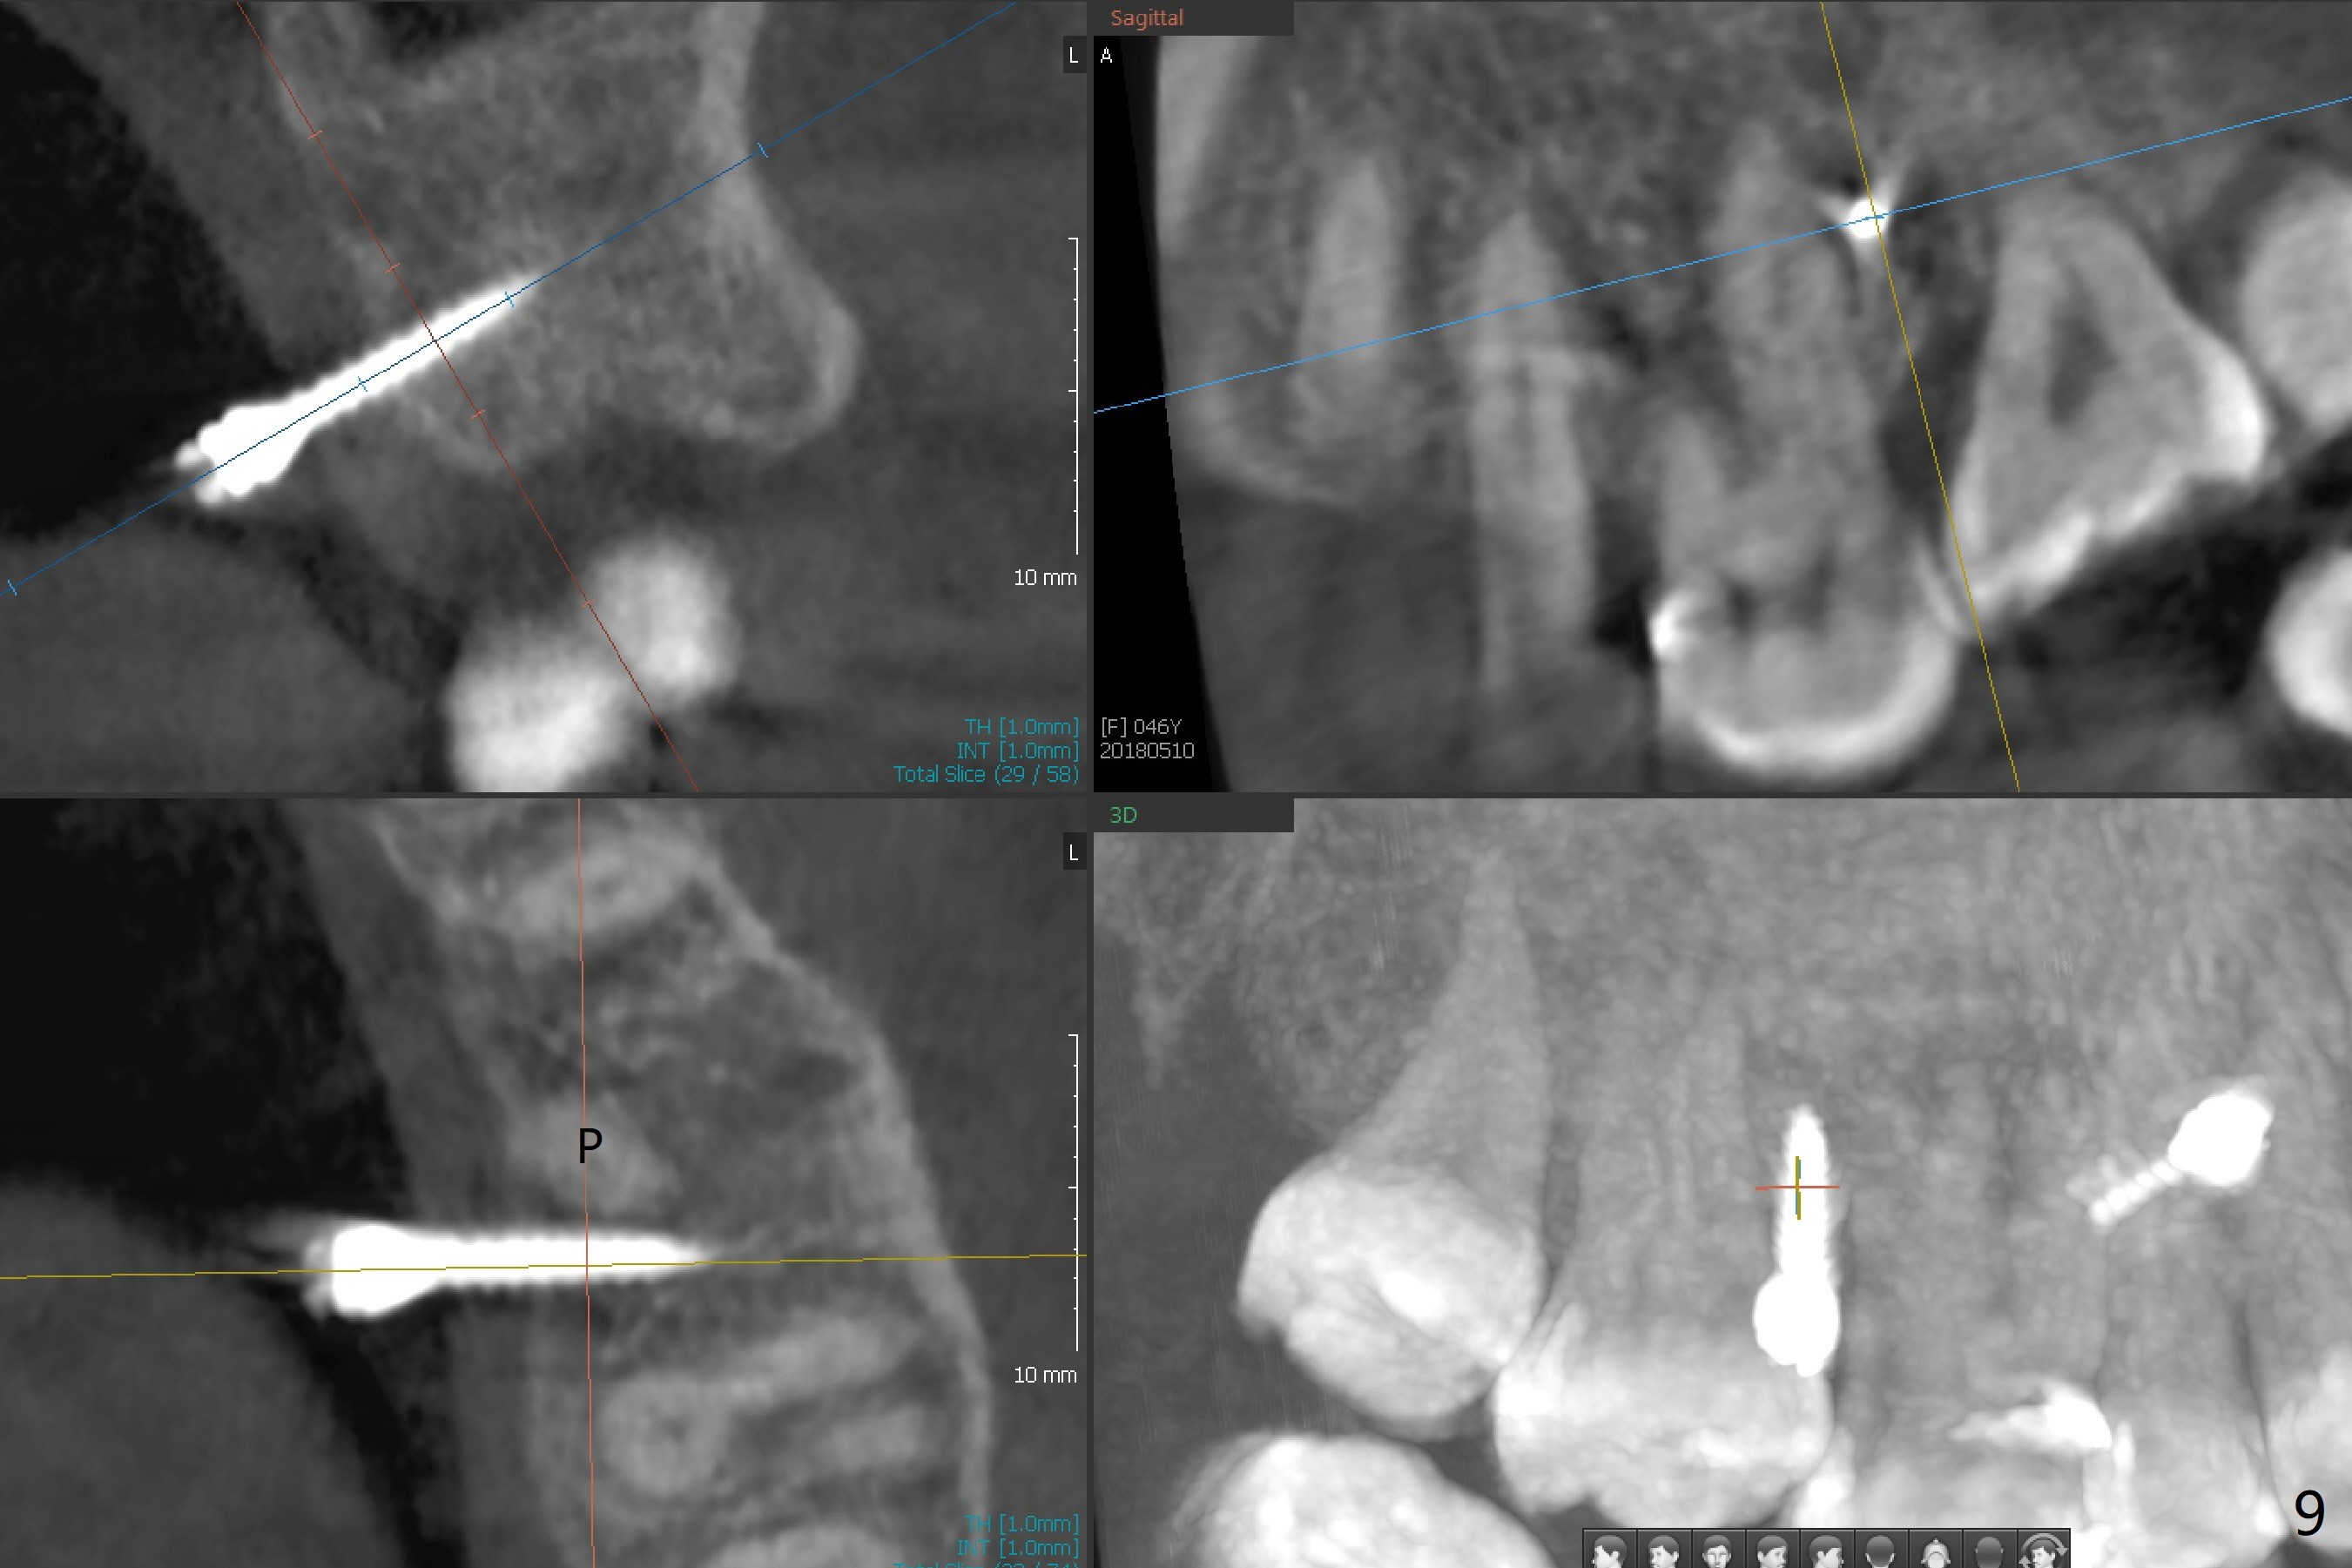

Fourteen days prior to implantation at #19 to replace a flipper (Fig.2), two minimplants are placed to intrude the supraerupted opposing tooth (#14, Fig.1). After use of minimal amount of local anesthetic (to keep proprioceptive in case root surface violation), the miniimplants are inserted ~ half of the length initially (Fig.3,4). The mesiobuccal (MB) one seems to be better positioned than the distopalatal (DP) one. When the implants are completely seated (Fig.5,6), three of PAs are taken, which suggests contact of the MB implant to the MB root of the tooth #14 (Fig.7 arrow). Immediately postop CT confirms approximation of MB and DP implants to the MB and P roots, respectively (Fig.8,9). The trajectory of these implants remain unchanged. Twelve days postop, the patient returns, uncomfortable with the palatal implant. After deep placement to bury the cuff (Fig.6) without local anesthesia (bone having no innervation), the patient feels better.